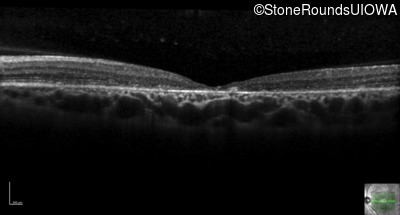

All three of the cardinal ophthalmic features of Mendelian macular dystrophies are present in this patient. The most striking features of the fundus exam are the numerous yellow flecks at the level of the RPE. Flecks are most commonly seen in AR Stargardt disease and pattern dystrophy although they may be seen in some of the rarer Mendelian maculopathies as well. The visual acuity in patients with AR Stargardt disease is often "worse than the fundus looks" while the acuity in pattern dystrophy is often quite good despite extensive flecks. The pedigree of this patient is compatible with ABCA4-associated Stargardt disease and the better than expected acuity is attributable to foveal sparing (see below). The onset of reduced acuity at age 10 is much more characteristic of ABCA4 disease than pattern dystrophy. Another feature present in this patient that is very frequently seen in Stargardt disease is peripapillary sparing. However, this sign can be seen in pattern dystrophy as well. When central atrophy is present in ABCA4-associated Stargardt disease it often somewhat shiny (which is uncommon with the geographic atrophy of pattern dystrophy or age-related macular degeneration). Some patients with ABCA4-associated Stargardt disease can have some preservation of the fovea giving a zonal "bullseye" appearance to the center of the macula. Sometimes this preservation is associated with preserved acuity as in this case. The outer nuclear layer (ONL) is much thinner than normal on OCT, indicative of photoreceptor loss. This is associated with a thinning of the ellipsoid zone which is usually many times brighter and thicker than the external limiting membrane (ELM). These two lines are essentially equal in intensity in this patient. The foveal sparing is seen on OCT only as a small bit of retinal convexity in the center of the atrophy coupled with a small bit of residual RPE flanked by bare Bruch's membrane. The presence of a robust I2e isopter on Goldmann perimetry places this patient in the least severe half of all Stargardt patients (see Schindler, et al., 2010). Most patients with ABCA4-associated disease are somewhat myopic as is this patient. Stargardt patients also tend to perform very poorly on pseudoisochromatic plates, even when their acuity is still fairly good as it is here.